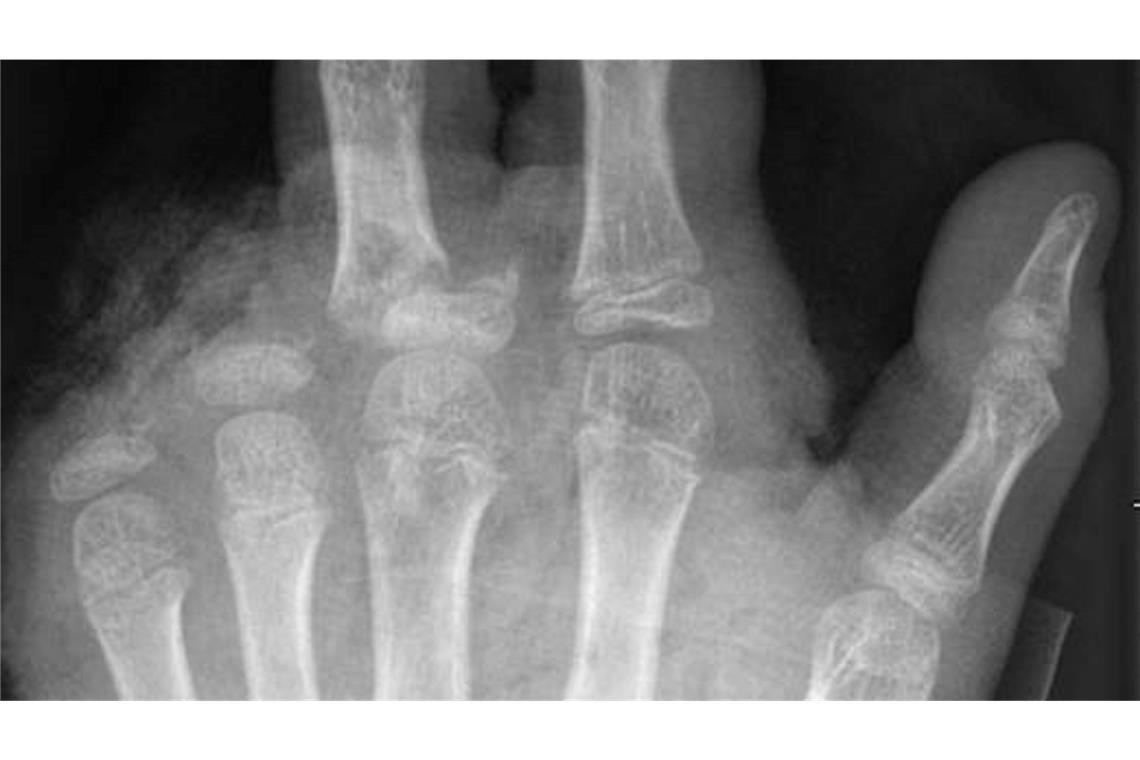

© -/UKB/dpa

So kann ein Röntgenbild nach einer missglückten Böllerexplosion aussehen: Zwei Finger fehlen.